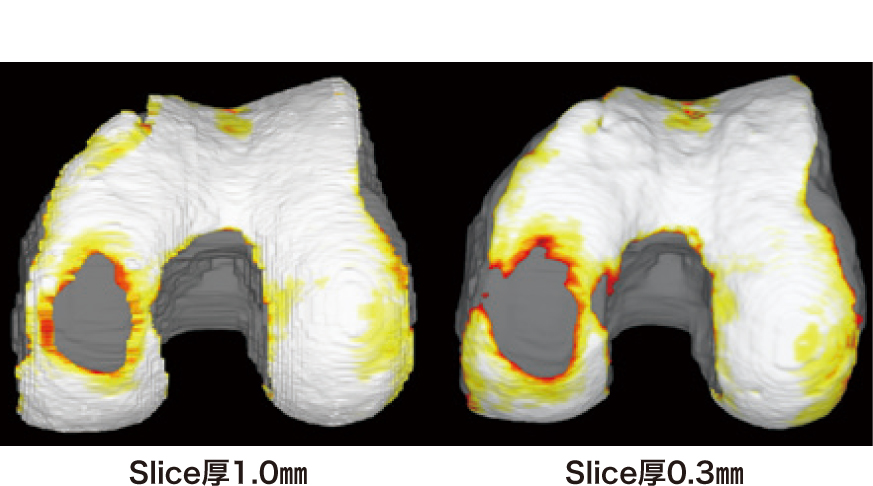

VINCENTで精度の高い解析を行うためには、一般的な膝MRIと比較しthin sliceでの撮像が必須となる。図4はsliceの設定の違いにより3D構築画像の精度が異なることを示した画像である。このように詳細な3Dの描出を行うためには、通常ルーティンで行う膝MRI撮像よりも時間を要するため、当院では膝関節解析導入前に予約枠の時間調整などMRI検査運用の見直しを行った。新設した「VINCENT膝関節MRI」枠は、遠方から来られた初診患者さまの対応を見越して作成したが、予約枠以上に検査依頼があり、患者さまの入れ替え時間を短縮するなど、できうる限りの対策を施して検査を回しているのが実情である。また、1シーケンス7~10分要するため、撮像中の体動によるアーチファクトや折り返しアーチファクトに細心の注意を払っている。患者さまへの十分な説明と最適かつ再現性あるポジショニングは我々技師の腕の見せ所である。

図4:Slice厚の設定の違い